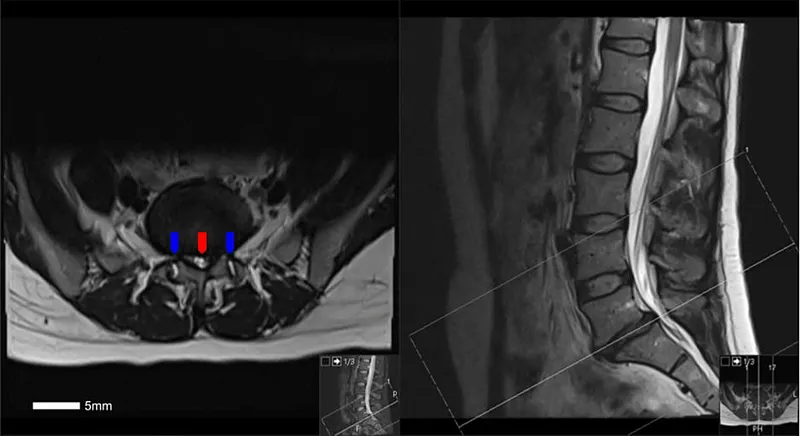

Spinal Stenosis Indian Medical PG Question 8: Investigation of choice for lumbar prolapsed disc -

- D. MRI (Correct Answer)

Spinal Stenosis Explanation: ***MRI***

- An **MRI** provides the best visualization of **soft tissues**, including the intervertebral discs, spinal cord, and nerve roots, making it the **gold standard** for diagnosing lumbar prolapsed disc.

- It can accurately show the **degree of disc herniation**, its impact on neural structures, and associated edema, which are crucial for treatment planning.